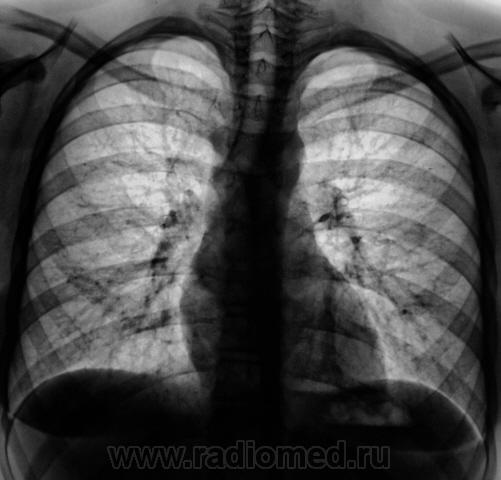

Ребенок направлен фтизиатром – «гиперпроба».

Ребенку 12 лет.

На левой верхушке очажки отсева.

Я написал бы очаги на 2 срезе в С1 с обеих сторон.

Единственное, что заставило задуматься, почему их (очаги) видно только на одном срезе.